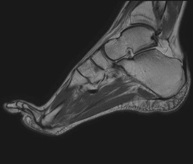

- Foot MRI

Examination for the study of injuries to tendons, muscles and small joints. Allows for effective assessment of cartilage injuries. It is also very useful for completing the preliminary ultrasound examination. It is a radiation-free procedure. It lasts approximately 20 minutes.